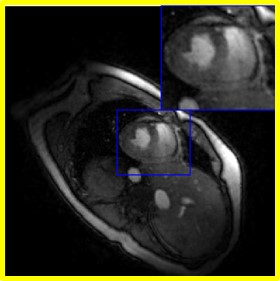

We also perform the comparisons on a different dataset in Fig. 8. We compare the proposed scheme with SToRM500, SToRM150, Time-DIP, and the low-rank approach. The results are shown in Fig. 8. From the figure, we see that the proposed reconstructions appear less blurred than those of the conventional schemes.

Refer to caption

(a) Visual comparisons

(b) Time profiles

Figure 8: Comparisons with the state-of-the-art methods. The first column of (a) corresponds to the reconstructions from 500 frames (similar-to\sim 25s of acquisition time), while the rest of the columns are recovered from 150 frames (similar-to\sim 7.5s of acquisition time). The top row of (a) corresponds to the diastole phase, while the third row is the diastole phase. The second row of (a) is an intermediate one. Fig. (b) corresponds to the time profiles of the reconstructions. We chose d=40𝑑40d=40 for the proposed scheme. We observe that the proposed reconstructions appear less blurred when compared to the conventional schemes.